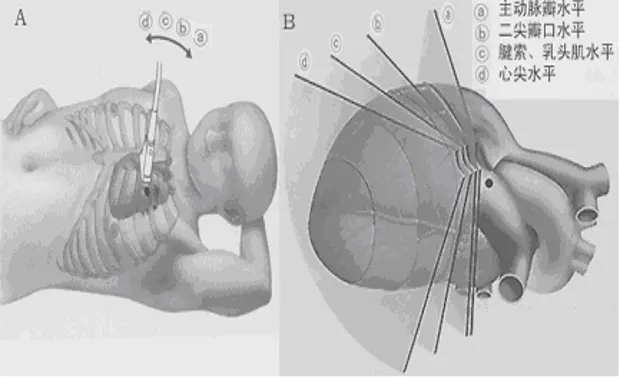

剑突下

● A为短轴切面,近似于人体矢状切面。

● B为长轴切面,近似于人体冠状切面。

剑突下四腔心切面

探头位置:探头位于剑突下声速指向左肩。

观察内容:4个房室腔;二尖瓣、三尖瓣、房间隔、室间隔。